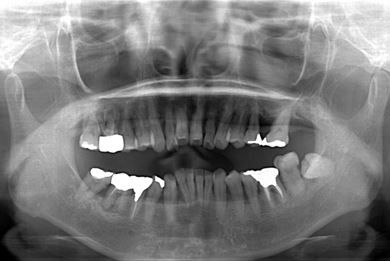

部分矯正治療+骨再生インプラント治療

| 性別/年齢 | 女性 / 52歳 | ||||||||||||||||||||||||||||||||

| 主訴 | 上前歯の歯並びが気になる | ||||||||||||||||||||||||||||||||

| 治療方針 | 全体的に骨が薄く、なるべく歯に負担を立てない治療計画にしました。口元も下げたいため、歯を少し細く削り後ろにさげました。部分矯正後、下顎のインプラントも併用しています。 | ||||||||||||||||||||||||||||||||

| 治療内容 | 部分矯正(唇側矯正ホワイト)、インプラント2本(GBR)、メタルボンドセラミッククラウン3本 | ||||||||||||||||||||||||||||||||